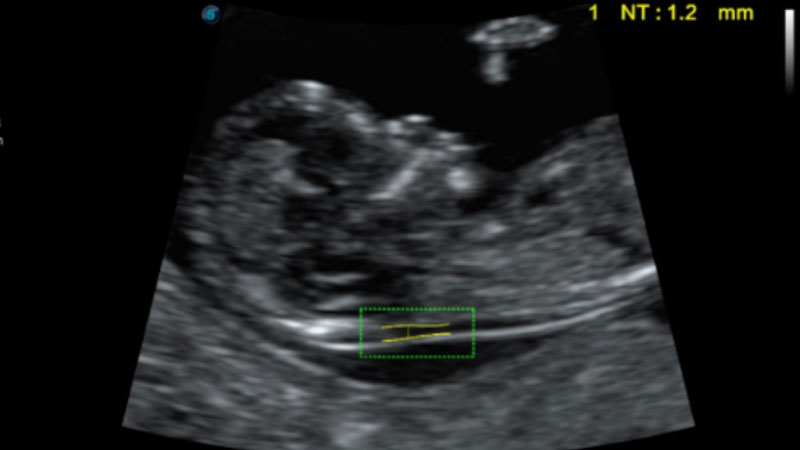

• NT自动测量

自动识别颈项透明层并获得NT值,为早孕胎儿畸形筛查提供有效测量工具,提高诊断效率和诊断信心。